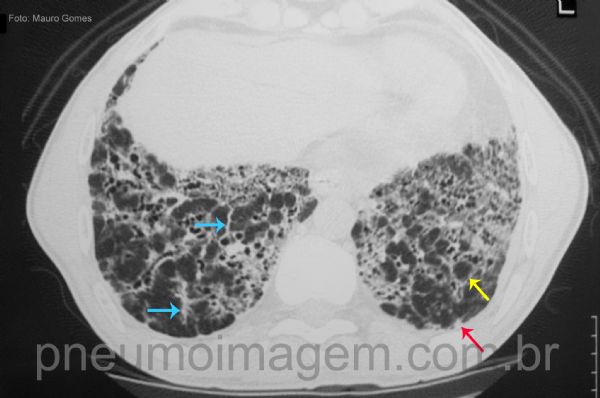

Na asbestose avançada os achados predominantes são de fibrose pulmonar, com faveolamento e bronquiectasias de tração. Espessamento septal interlobular (seta amarela), bandas parenquimatosas (seta azul) e nódulos puntiformes subpleurais (seta vermelha) também são visíveis.

In advanced asbestosis, the predominant findings are pulmonary fibrosis, with honeycombing and traction bronchiectasis. Interlobular septal thickening (yellow arrow), parenchymal bands (blue arrow) and subpleural punctate nodules (red arrow) are also visible.

Chaves: honeycombing; honeycomb lung; interlobular septal thickening (yellow), parenchymal bands (blue); subpleural nodules (red).